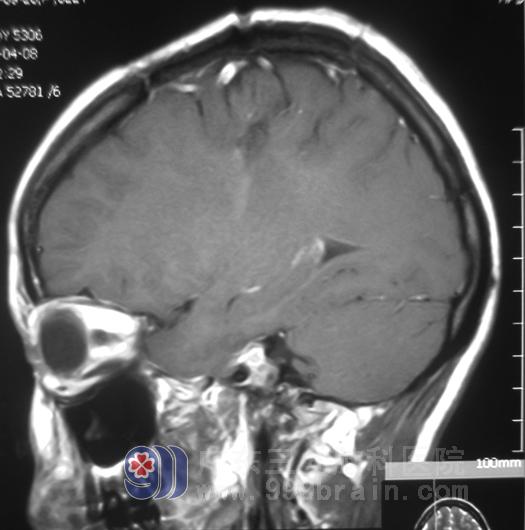

家属同意后,由鲁明主任主刀,在唤醒麻醉下行右侧额顶叶脑内血肿+病变组织切除术。术前导航,术中见血肿腔周围杂乱血管团,再次导航定位病变组织,唤醒下病变组织顺利切除。术后小燕头痛头晕症状好转,能独立行走,未出现功能障碍。术后病理:动静脉畸形。

手术后